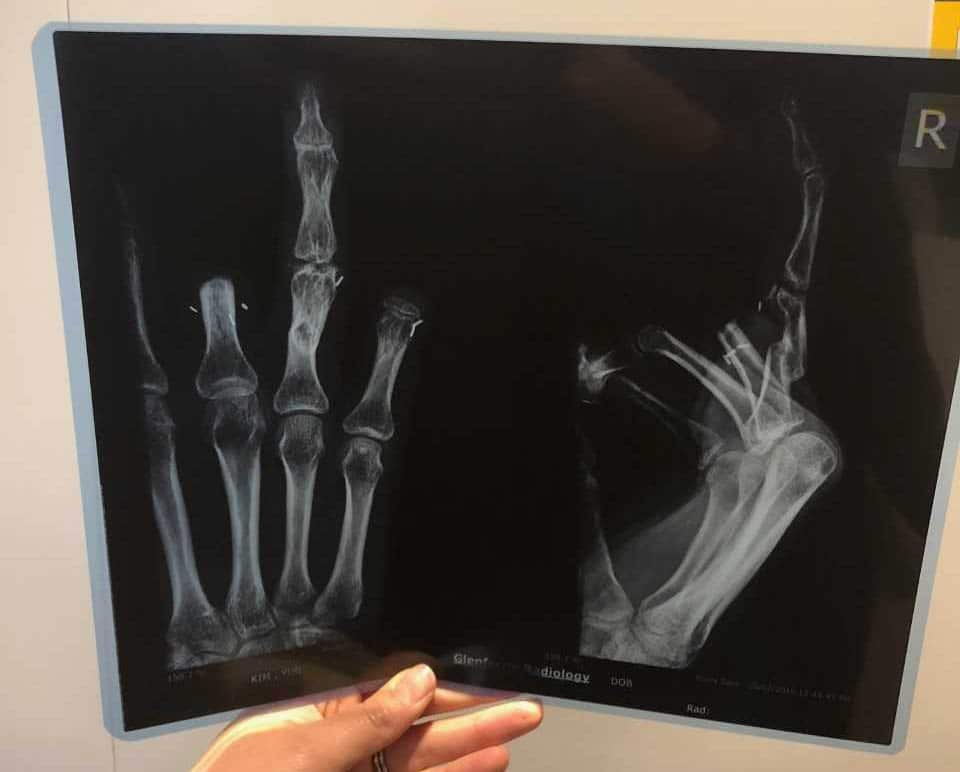

Five of her fingers – three on one hand, two on the other – had to be amputated, two down to her knuckles. Her ring finger on her left hand was successfully re-attached, but its function is limited.

While her prosthetic fingers assist with aesthetics, they provide little function.